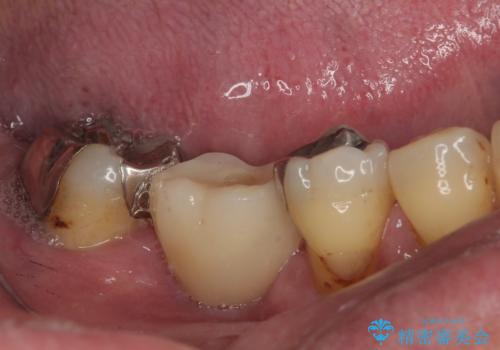

- 奥歯を抜歯してから放置しているとのことで来院された患者様です。

歯が割れて抜歯になってしまったとのことで、咬合力に抵抗できるよう、インプラントによる補綴治療を行うこととしました。

むし歯の放置期間と抜歯してからの放置期間が長く、咬み合わせる上顎の歯がやや伸び出している状態でした。

上顎の部分矯正や対合歯の補綴治療も提案しましたが、今回は欠損部のみの治療を行いました。